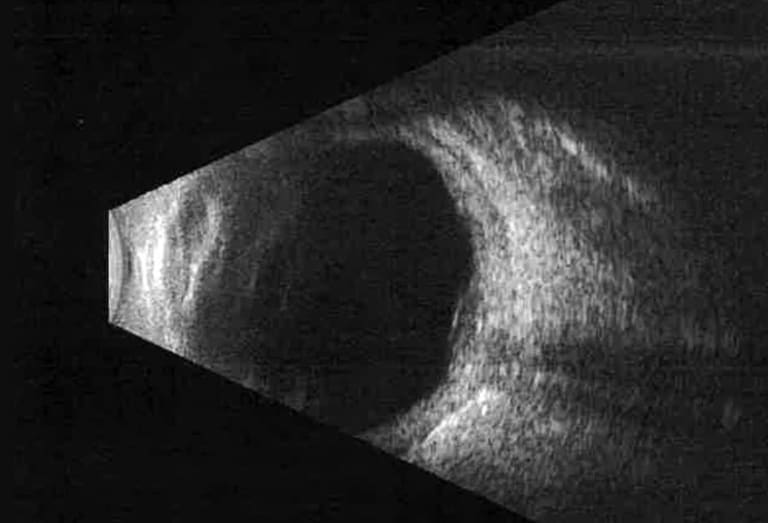

Abb. 4: B‑Bild-Sonographieuntersuchung des rechten Auges mit Verdickung des Netzhaut-Aderhaut-Sklera-Komplexes und T‑Zeichen bei Diagnosestellung 2023.